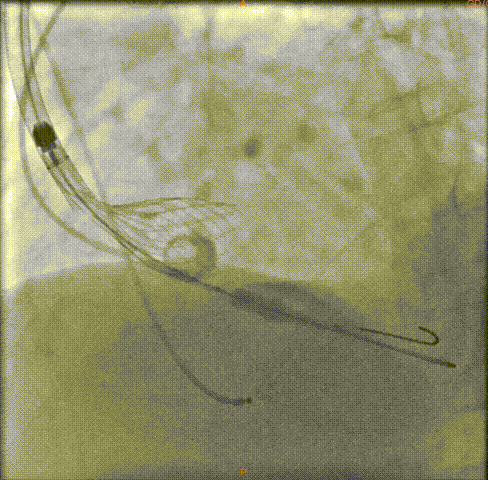

瓣膜完全释放前造影

完全释放中造影

释放后的造影